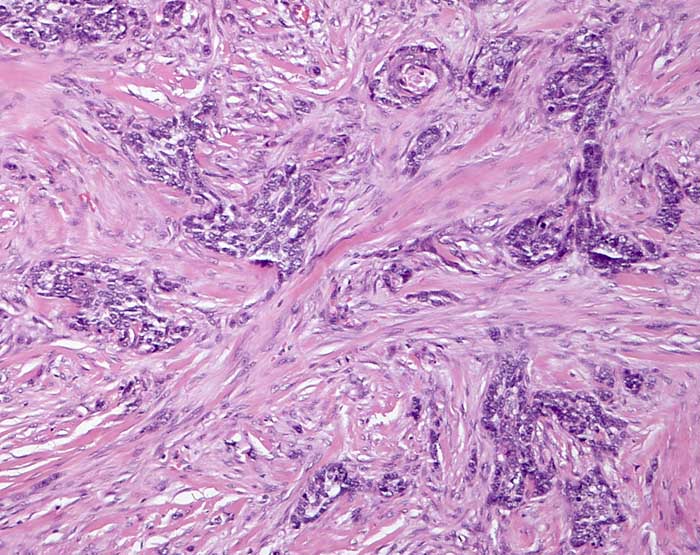

PathoPic ID 7680 - infiltratives sklerodermiformes Basaliom

infiltratives sklerodermiformes Basaliom

Haut, Rumpf

Haut

Basaloide Zellkomplexe werden von reichlich desmoplastischem Stroma komprimiert.

Basaliom mit porzellanartiger weiss glänzender Oberfläche.

Dieser Tumor ist oft ausgedehnter als klinisch sichtbar. Die Schnittrandkontrolle muss deshalb intraoperativ mit Schnellschnitt erfolgen.

Histologie

100